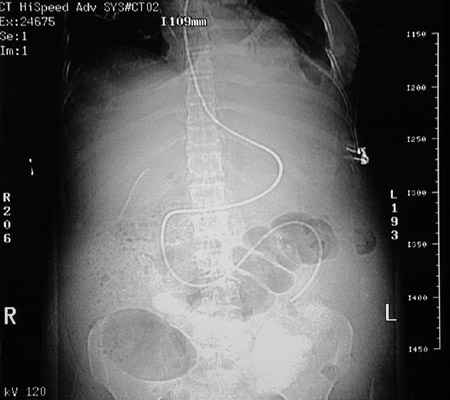

In this coronal CT scan view can be seen a long feeding tube positioned in the upper GI tract. There is prominent gas in the colon.